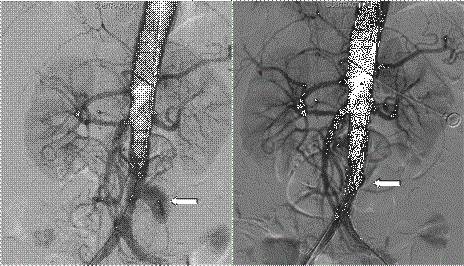

75岁的周老先生半年前出现咳嗽、咳痰、胸痛等不适,一直以为是感冒,没有引起重视,间断治疗半年也不见好转,后辗转来到长沙市中心医院肺科医院就诊,经肺部CT、痰培养等一系列检查下来,确定是肺空洞型结核,马上开始抗结核治疗。治疗没几天,患者出现腹痛,再次行腹部CT检查发现腹主动脉瘤。请普外科的血管外科周杰斌副主任医师会诊并完善主动脉CTA检查后,周教授当即决定转科手术治疗。

患者由肺科医院转入我科,经术前评估,患者为高龄,合并慢性阻塞性肺疾病、肺部感染及房颤,加之肺结核的影响,肺功能很差,不能耐受全麻手术。周教授在仔细阅片后认为假性动脉瘤破口位于左侧肾动脉开口下方约6cm,紧邻双侧髂总动脉,周围组织结构不清,存在炎性病灶可能,结合患者病史,不排除结核性血管炎,血管置换存在感染风险,决定局部麻醉下行腹主动脉支架腔内隔绝术,用最小的创伤解除患者假性动脉瘤随时可能破裂出血的风险。手术由周杰斌、曾赟裘副主任医师配合完成,切开皮肤,置入血管鞘、导丝及导管,血管造影,置入覆膜支架隔绝瘤体,再次造影确认等这一系列步骤一气呵成,一个小时便顺利完成手术,术后患者腹痛症状消失。